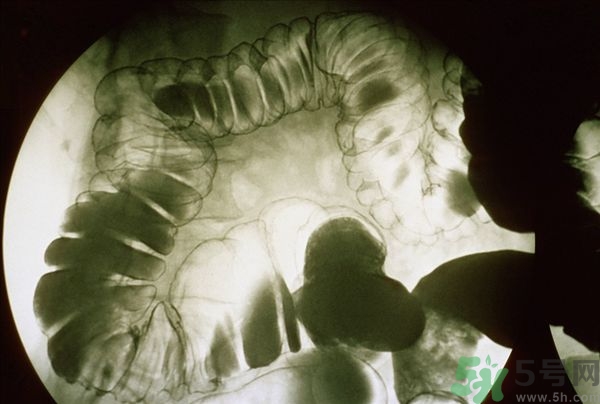

腸炎的分類其實有很多,比如盲腸炎、潰瘍性大腸炎、慢性腸炎、急性腸炎等等,是比較常發(fā)生的胃腸疾病,當我們的腹部出現(xiàn)劇痛的時候首先我們要確定是哪一種疾病,并且要及時的進行治療,腸炎嚴重的時候甚至有休克的可能,下面我們就來說說當腸炎患者出一了腹前的時候應該怎么緩解與治療。

腸炎的主要癥狀

(1)消化道癥狀

常呈現(xiàn)間斷性腹部隱痛、腹脹、腹痛、腹瀉為本病主要表現(xiàn)。遇冷、進油(油食品)膩之物或遇情緒波動、或勞累后尤著。大便次數(shù)增加,日行幾次或數(shù)十余次,肛門下墜,大便不爽。慢性腸炎急性發(fā)作時,可見高熱、腹部絞痛、惡心嘔吐、大便急迫如水或粘凍血便。

(2)全身癥狀

呈慢性消耗癥狀,面色不華精神不振,少氣懶言,四肢乏力,喜溫怕冷。如在急性炎癥期,除發(fā)熱外,可見失水、酸中毒或休克出血表現(xiàn)。

(3)體征方面

長期腹部不適或少腹部隱隱作痛,查體可見腹部、臍周或少腹部為主,有輕度壓痛、腸鳴音亢進、脫肛。